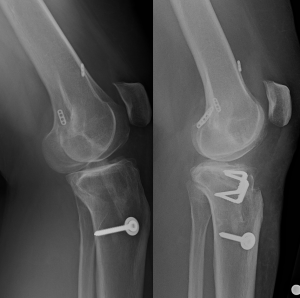

In the multiple revision patient, it is even more important to determine the reason for failure to ensure the same mistakes are not repeated. The surgeon must be prepared to expand the scope of possible interventions. For example, we present a case of a 41-year-old female with a history of a failed primary hamstring autograft ACL reconstruction, followed by a failed bone-patellar tendon-bone allograft revision ACL reconstruction (Figure 4). She presented with knee pain and recurrent instability. As part of her preoperative evaluation, posterior tibial slope was measured at 17°. Therefore, in addition to anatomic revision ACL reconstruction, an anterior tibial closing wedge osteotomy was performed to decrease the excessive posterior tibial slope and decrease the strain on the ACL (59). Multiple revision cases, such as this example, highlight the importance of a thorough preoperative plan and execution.